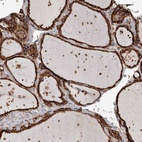

Immunohistochemical staining of human thyroid gland shows strong cytoplasmic positivity in glandular cells.